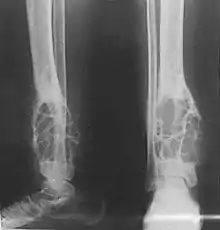

Histologically, islands of epithelial cells are found in a fibrous stroma. The tumor is typically well-demarcated, osteolytic and eccentric, with cystic zones resembling soap bubbles.[2]

Diagnosis is on plain radiography, or CT scan